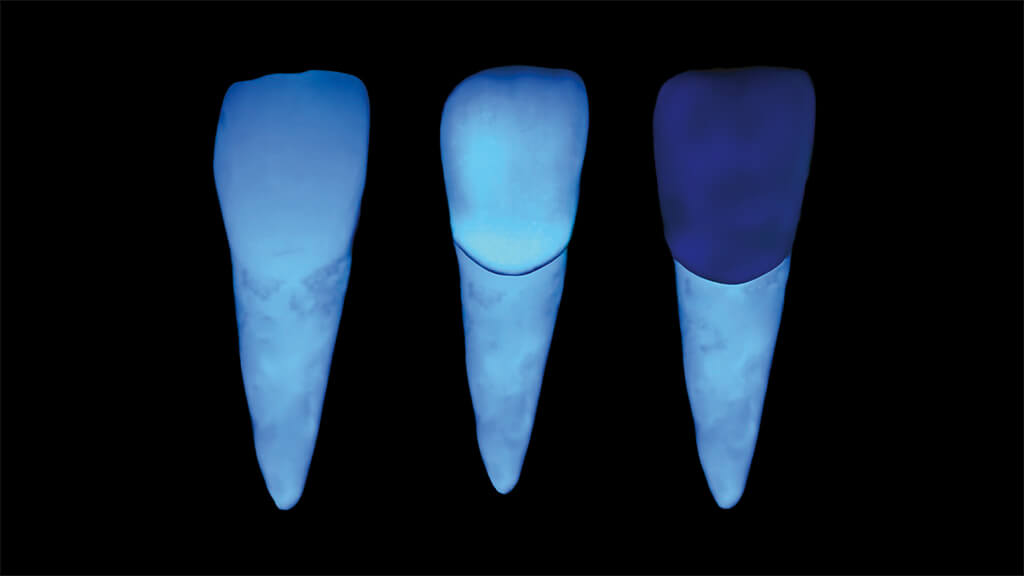

Nachdem die Aufnahme unter Reflexionen durchgeführt wurde, wird auf eine andere Kamera gewechselt. Bei dieser ist vor dem Ringblitz ein polar_eyes-Kreuzpolfilter angebracht, sodass wir polarisierte Aufnahmen anfertigen können. Erneut wird zunächst eine Aufnahme für den Weißabgleich angefertigt (Abb.62) und anschließend eine Aufnahme des gesamten Frontzahnbereichs mit Kontrastplatte (Abb.63). Der Hauptvorteil der Kreuzpol-Fotografie besteht darin, dass die Zahnfarbe, insbesondere den Grundfarbton besser beurteilt werden kann. Wie bei den Aufnahmen mit dem Lateralblitz werden auch bei den Kreuzpolfilter-Aufnahmen die Farbmuster neben die natürlichen Zähne gehalten und die Aufnahmen angefertigt (Abb.64 und 65). Man beachte, dass auf beiden Aufnahmen der Metallgriff des Farbmusters schwarz erscheint. Der Grund hierfür ist der, dass mit dem Kreuzpolfilter jegliche Reflexion ausgeschaltet wurde, welche die tatsächliche Farbe der metallischen Legierung zeigt.